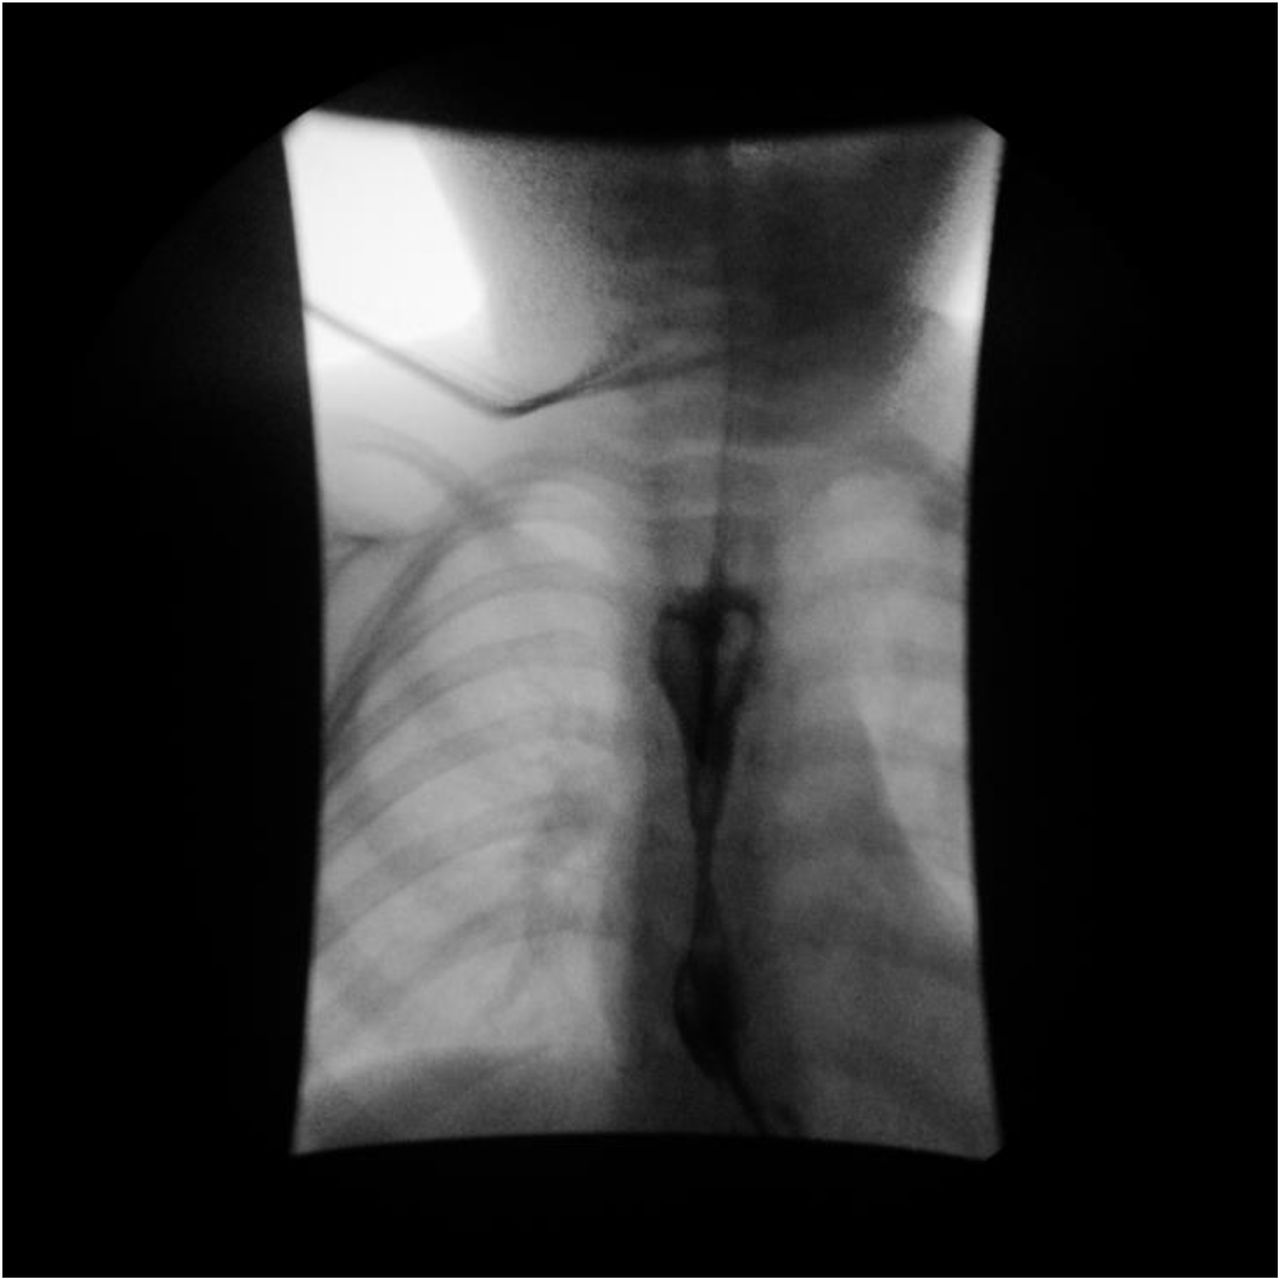

- Stricture (Figure 3)

Figure 3. Esophagram obtained in a 3-year-old male patient demonstrates smooth tapering of the distal esophagus at the T7-8 level, which is compatible with esophageal stricture. The smooth appearance without any areas of mucosal irregularity or ulceration suggests a congenital etiology or prior caustic esophageal injury. An enteric tube was used to introduce contrast material, as the patient refused to drink it. Pathology revealed esophagitis with basal cell hyperplasia, >36 eosinophils per high-powered field, subepithelial fibrosis, and papillary sclerosis. The patient was diagnosed with EoE, and budesonide slurry was started.

Figure 3. Esophagram obtained in a 3-year-old male patient demonstrates smooth tapering of the distal esophagus at the T7-8 level, which is compatible with esophageal stricture. The smooth appearance without any areas of mucosal irregularity or ulceration suggests a congenital etiology or prior caustic esophageal injury. An enteric tube was used to introduce contrast material, as the patient refused to drink it. Pathology revealed esophagitis with basal cell hyperplasia, >36 eosinophils per high-powered field, subepithelial fibrosis, and papillary sclerosis. The patient was diagnosed with EoE, and budesonide slurry was started.

From Zucker EL, Nagendra G, Bhardwaj V. A 3-year-old male with unusual esophageal stricture. Pediatrics. 2020;146:471-472.